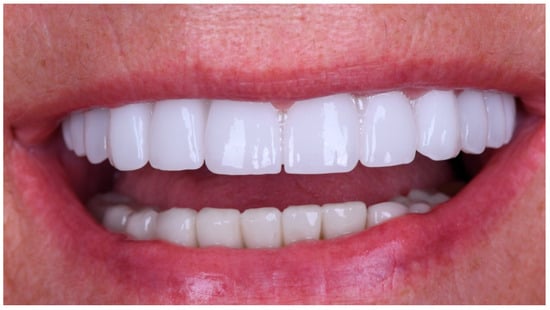

Figure 18. Extraoral frontal view of the definitive full-arch prosthesis in situ, demonstrating the final aesthetic outcome.

The definitive prosthesis was delivered to the patient after laboratory verification. Intraoral evaluation confirmed accurate seating, passive fit, and proper occlusal relationships. Phonetics and aesthetics were reassessed and found to be satisfactory, consistent with previous retrospective data showing high survival rates and patient satisfaction with zirconia-based full-arch prostheses [28]. A panoramic radiograph was obtained at the time of prosthesis delivery to confirm the correct seating of the framework–zirconia assembly on all supporting implants, as well as to verify stable peri-implant bone conditions.

The restoration was torqued in line with the manufacturer’s specifications, and the screw access channels were sealed with composite resin. The definitive clinical situation in the patient’s mouth is shown in Figure 18 and Figure 19.

Static and dynamic occlusion were subsequently assessed using a digital OccluSense pressure analysis system (Bausch, Hainspitz, Germany).A follow-up was scheduled after 4 months, and the prosthesis demonstrated stable function and satisfactory aesthetics. The patient was fully satisfied.